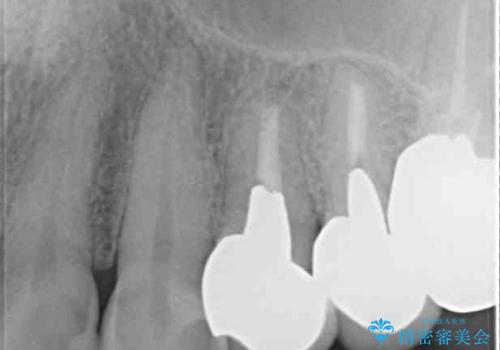

- 歯肉が退縮したためにクラウンの縁や歯根が見えてしまっていることを気にして来院された患者様です。

強い咬合力や磨きすぎなどにより、歯根が見えてしまったり、金属の縁が見えてしまったりし、審美障害を引き起こすことがあります。

歯根が変色してしまうと、歯肉越しに歯根の黒い色が透けてしまうことがあり、この点についてはどうにも施しようがないため、患者様には事前のご理解いただきました。